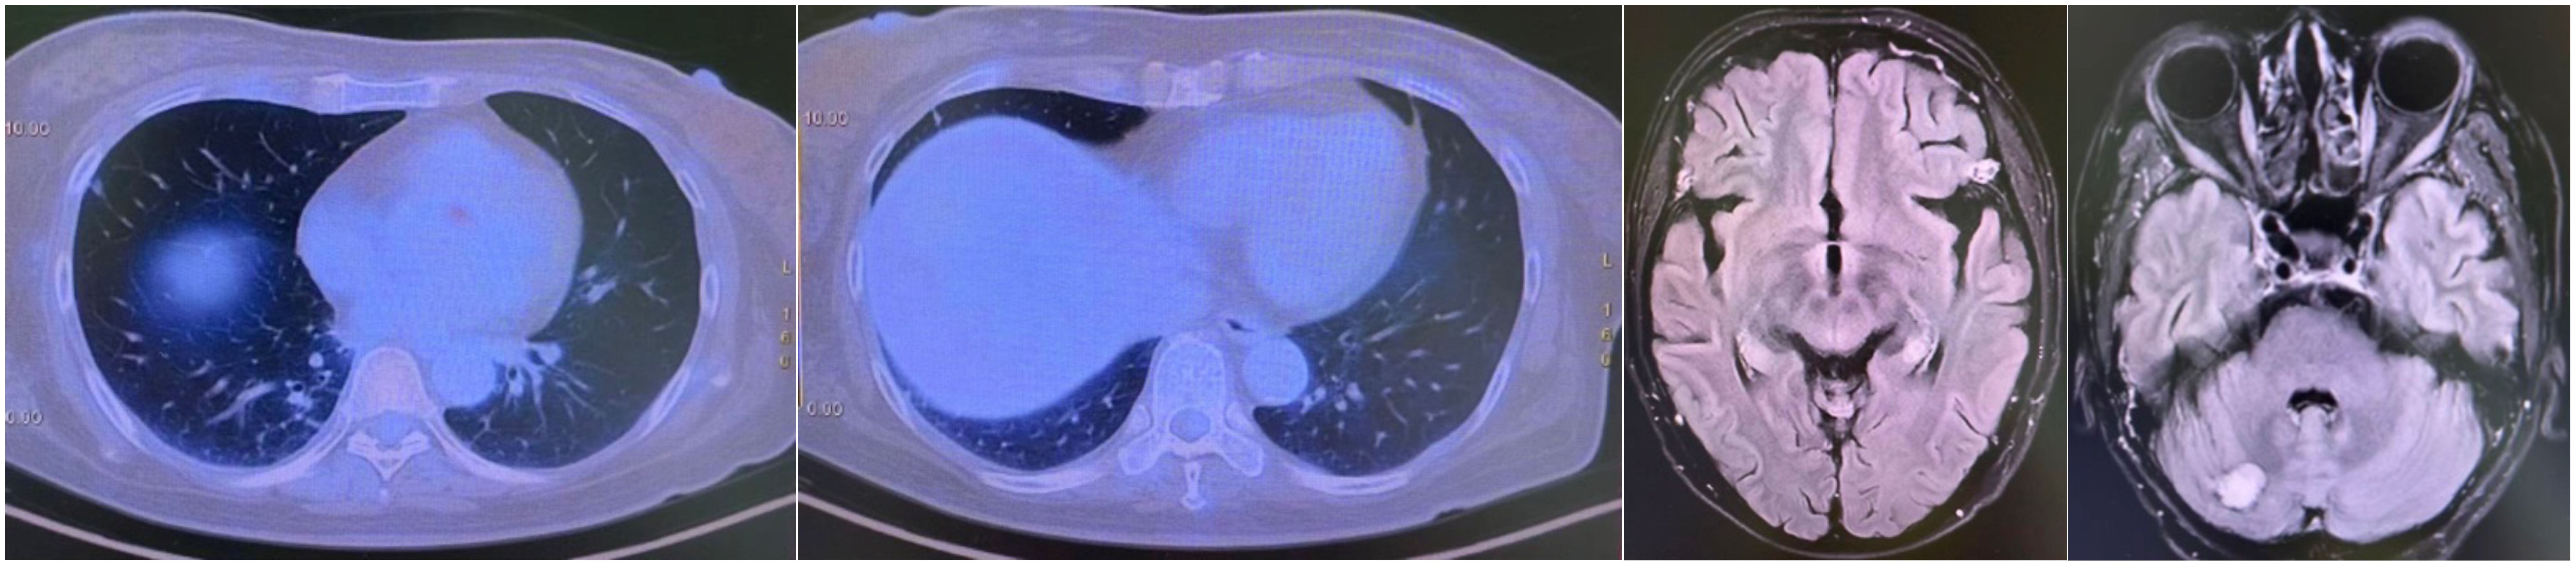

A CT-guided biopsy revealed transformation to small-cell lung cancer with maintained neuroendocrine marker expression. Second-line therapy with etoposide (100 mg/m² days 1-3) and cisplatin (75 mg/m² day 1) was administered for four cycles (9). CT scans showed that the lung lesions had significantly shrunk. (Figure 2) The patient subsequently received consolidative radiotherapy: whole-brain radiotherapy (39 Gy in 13 fractions) followed by intensity-modulated radiotherapy to the primary lung tumor (45 Gy in 30 fractions) (10, 11). Histological analysis from a re-biopsy of the progressive chest lesion revealed small cell cancer transformation and tested positive for neuroendocrine markers, including synaptophysin, chromogranin A, and CD56. Tissue and blood samples were subjected to next-generation sequencing (NGS), which revealed an EGFR exon 21 L858R deletion. In March 2021, PET/CT and brain MRI revealed new metastatic lesions in the pleura and liver capsule, with an increase in multiple metastatic tumors in the brain. (Figure 3) Serum tumor markers showed elevated carcinoembryonic antigen (CEA) (8.1 ng/mL) while NSE remained normal (11.3 ng/mL). Following disease progression, a third biopsy of the chest mass was performed, but no tumor tissue was detected. Circulating tumor DNA (ctDNA) from peripheral blood revealed an EGFR exon 21 L858R deletion. We considered that the recurrent focus might be adenocarcinoma of the lung. Plasma ctDNA analysis confirmed persistence of EGFR L858R mutation without additional resistance alterations. Third-line therapy (from April 20 to July 21, 2021) with paclitaxel (200 mg/m²), carboplatin (AUC 5), and bevacizumab (15 mg/kg) was administered every three weeks (12). After four cycles, CEA decreased to 3.9 ng/mL, and CT imaging showed a partial response (Figure 4). Treatment was complicated by grade 2 epistaxis, leading to bevacizumab discontinuation. The patient was switched to maintenance therapy with aumolertinib (110 mg daily) combined with anlotinib (12 mg daily, days 1–14 every 21 days) (13, 14). Follow-up assessments at 2, 6, 10, and 14 months showed sustained clinical and radiographic stability. The patient ultimately died due to progressive brain metastases in November 2022, with an overall survival of 48 months. The course of treatment is presented in Figure 5.

Figure 2

Four medical scans in sequence. The first two are chest CT scans, showing cross-sections of the thoracic cavity with lungs visible. The last two are brain MRI scans, displaying axial views with brain structures in varying shades of gray.

Figure 2. Partial response after etoposide and cisplatin #4.